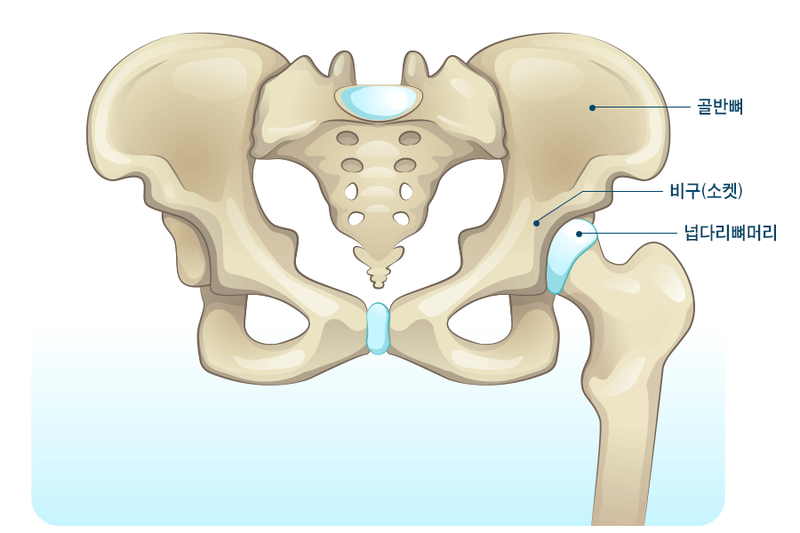

고관절은 엉덩이관절이라고도 불리우며, 보통 알고있는 골반위치에 있고, 공처럼 둥글게 생긴 대퇴골두가 글러브가 감싼듯한 모양으로 비구에 맞물려 있어요.

이렇듯 고관절은 오목하게 들어간 비구와 둥근 공모양의 대퇴골두로 이루어져 있으며 골반과 다리를 이어주는 우리 몸의 핵심 관절인데요. 그리고 고관절은 골반을 통해 전달되는 체중을 지탱해주고 걷기와 달리기같은 다리 운동들을 가능하게 해주는 관절이기도 해요.